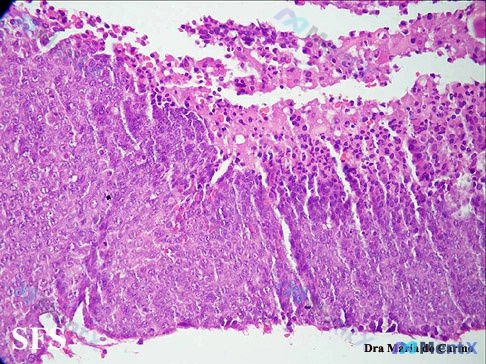

无角化珠的嗜酸性细胞巢,是鳞癌还是黑色素瘤?这张HE切片的分析逻辑值得一看

在论坛上看到一张很有讨论价值的HE染色病理切片,整理了一下自己的分析思路,和大家分享。 先看一下切片里的关键形态学表现 1. 整体结构 - 正常的分层结构完全消失,取而代之的是大片增生的细胞 - 细胞排列紧密、拥挤,呈片状/弥漫性生长,缺乏正常连接 - 局部可见坏死、脱落及少量炎细胞浸润 2. 细胞...